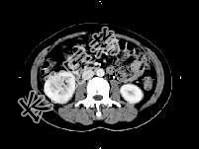

- 单项选择题女,27岁, 寒战高热、尿频、尿痛3天,尿检: 白细胞(+++),CT平扫及增强扫描如图所示, 下列说法错误的是 ( )

A、右肾体积增大

B、增强后右肾实质内可见条片状密度减低区

C、左肾未见异常

D、考虑为急性肾盂肾炎

E、考虑为慢性肾盂肾炎